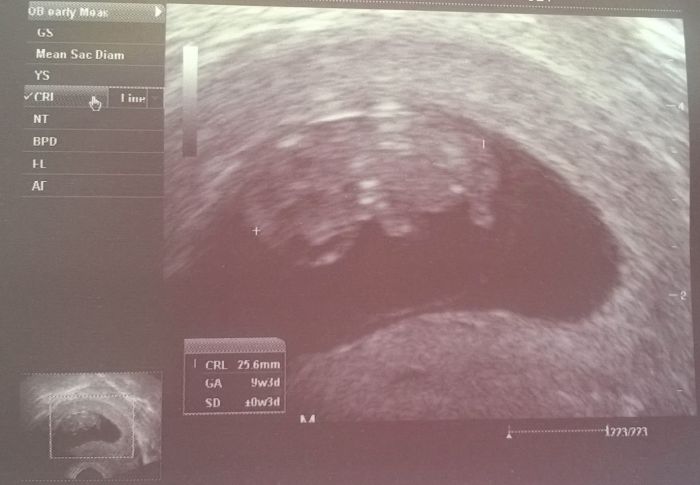

[746937] No já naše bábi obdivuju vůbec ... ona ta doba měla něco do sebe :-) Přijde mi to teď takový jako na běžícím páse všechno ... Tohle smíš nesmíš, a ony byly až do porodu na poli a pracovali. I když věřím že je tu spousta holek co těžce pracuje. Přídávám taky fotku našeho chalupáře (máme s přítelem takový "pracovní" název protože jsme si ho umylem udělali na chatě po lahvince vína :-D ) Jinak všem dnes gratuluji k dobrým výsledkům, oslavím to večer nealko pivem a knedlíkama se zelím